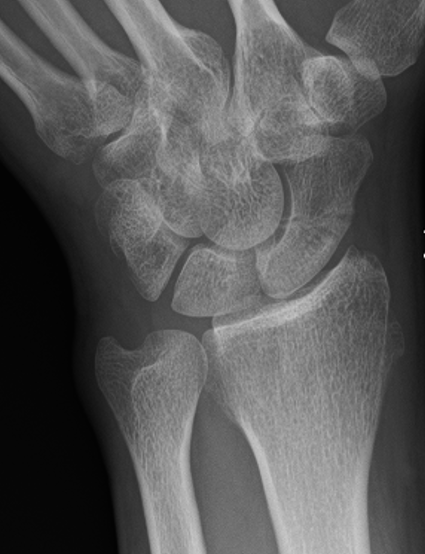

Nonunion with minimal displacement and minimal resorption

Nonunion with significant displacement and bone resorption

Proximal pole fracture with displacement and absorption